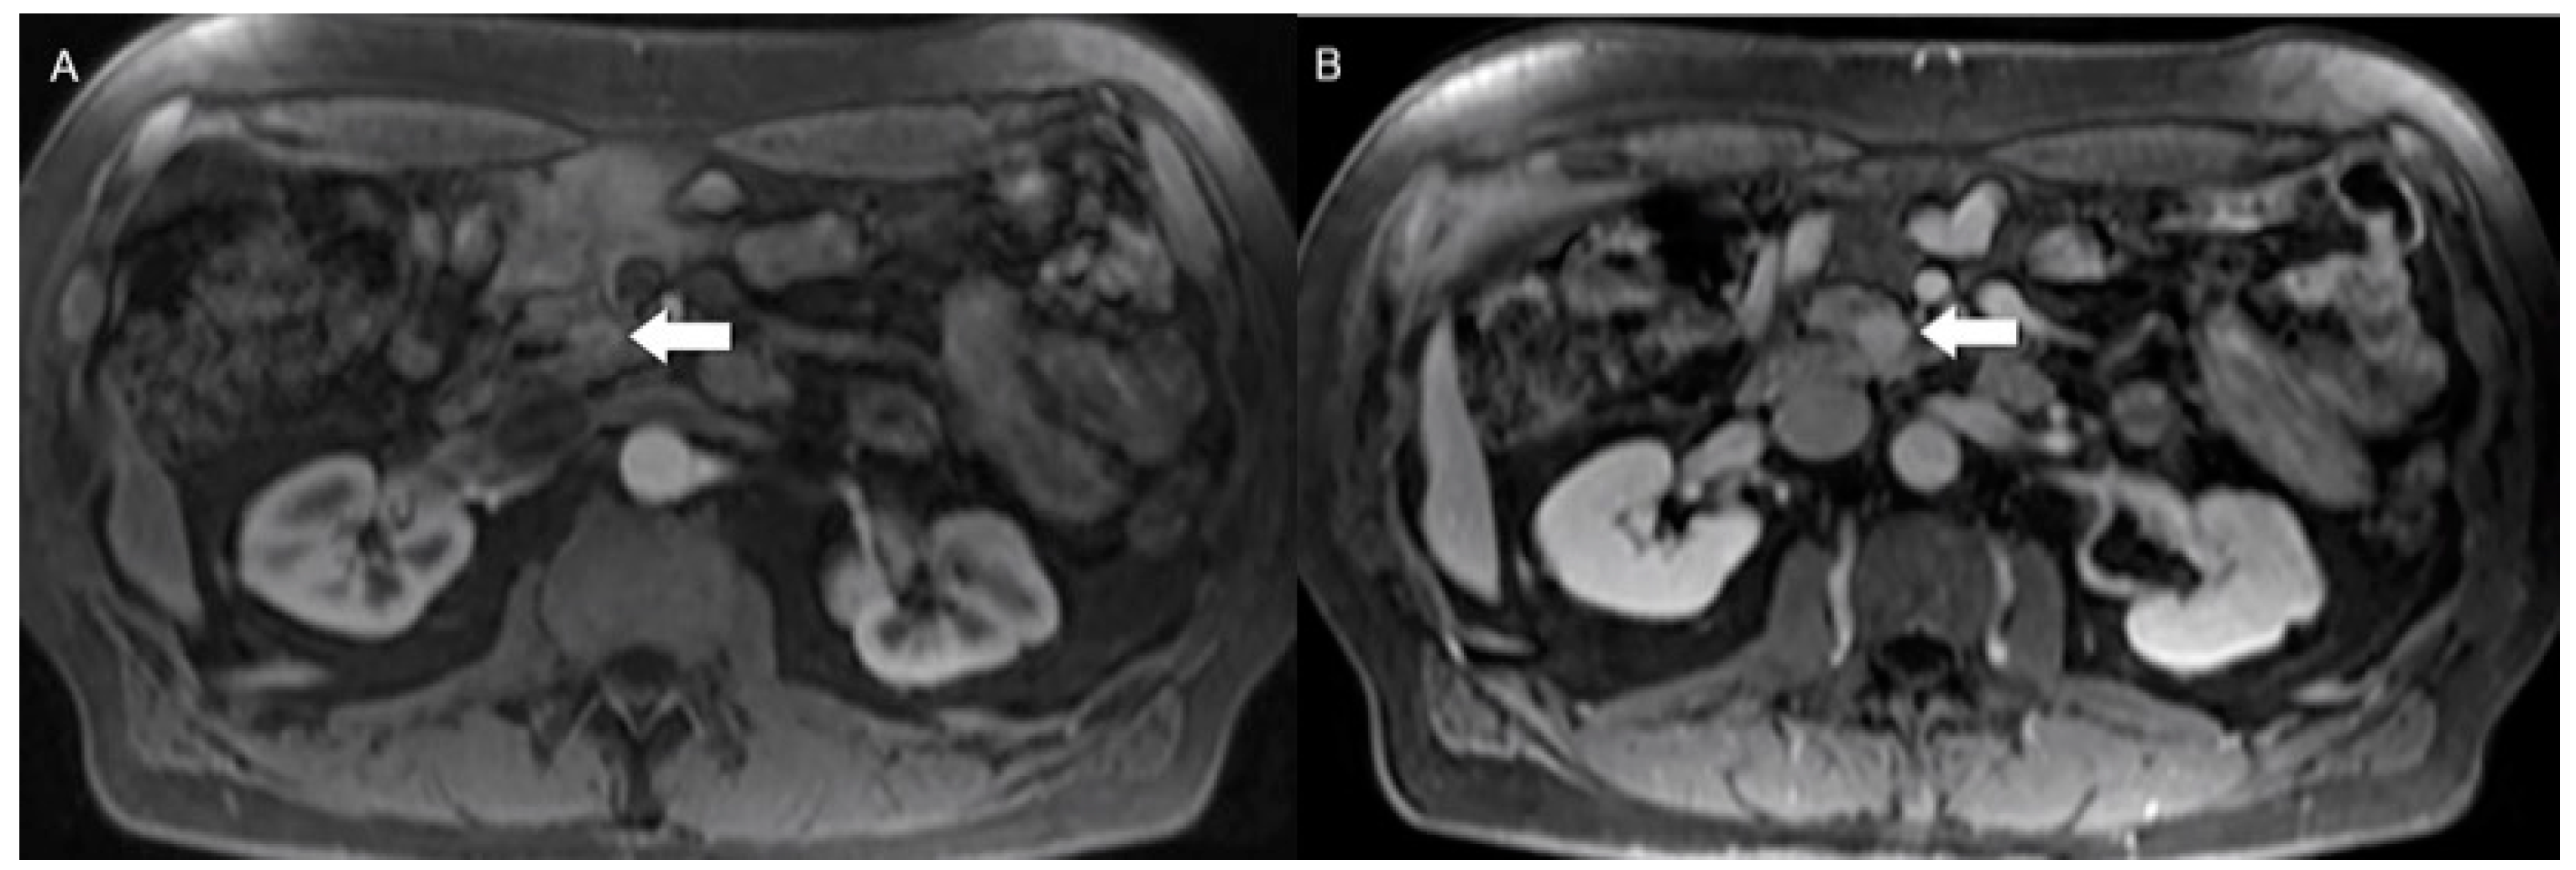

- Hwang, E.J.; Lee, J.M.; Yoon, J.H.; Kim, J.H.; Han, J.K.; Choi, B.I.; Lee, K.-B.; Jang, J.-Y.; Kim, S.-W.; Nickel, M.D.; et al. Intravoxel Incoherent Motion Diffusion-Weighted Imaging of Pancreatic Neuroendocrine Tumors. Investig. Radiol. 2014, 49, 396–402. [Google Scholar] [CrossRef] [PubMed]

- Mebis, W.; Snoeckx, A.; Corthouts, B.; El Addouli, H.; Nicolay, S.; Van Hoyweghen, A.; Spinhoven, M.; de Beeck, B.O. Correlation Between Apparent Diffusion Coefficient Value on MRI and Histopathologic WHO Grades of Neuroendocrine Tumors. J. Belg. Soc. Radiol. 2020, 104, 7. [Google Scholar] [CrossRef] [PubMed]

- Zong, R.L.; Geng, L.; Wang, X.; Xie, D. Diagnostic Performance of Apparent Diffusion Coefficient for Prediction of Grading of Pancreatic Neuroendocrine Tumors. Pancreas 2019, 48, 151–160. [Google Scholar] [CrossRef] [PubMed]